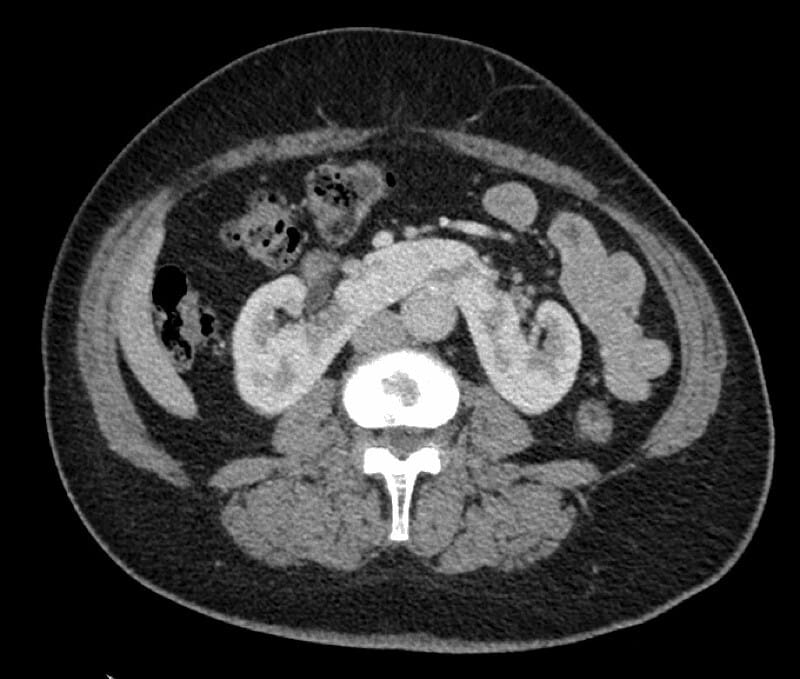

This is an axial CT image showing a horseshoe kidney, characterized by fusion of the lower poles of both kidneys across the midline anterior to the aorta.

- CT: Demonstrates fused lower poles across midline with enhancing renal parenchyma isthmus anterior to aorta; abnormal kidney orientation with medial lower poles; excretory phase shows malrotated pelvicalyceal systems; possible identification of accessory vessels and assessment of complications like PUJ obstruction, stones

- Signs: Isthmus signโrenal tissue band crossing the midline anterior to the aorta; Reverse renal rotationโlower poles oriented medially rather than laterally; abnormal renal axis and low position in abdomen